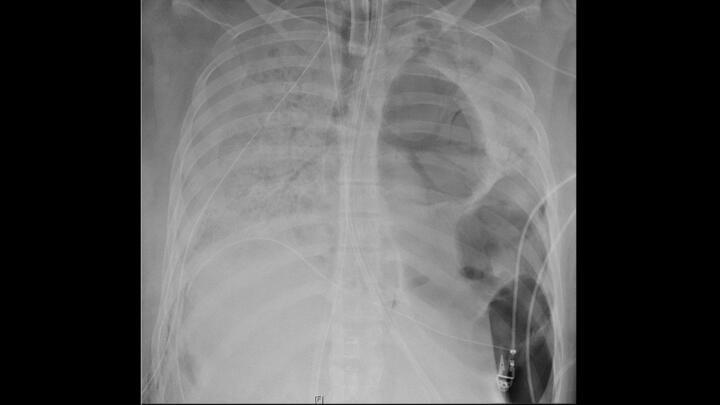

La Radiografia De Torax En La Unidad De Cuidados Intensivos Imagen Diagnostica

Http Educacionensalud Imss Gob Mx Es System Files 2 Hallazgos En Radiografia De Torax Pdf

Falso Neumomediastino En Radiografia De Torax Medicina Intensiva

www.medintensiva.org